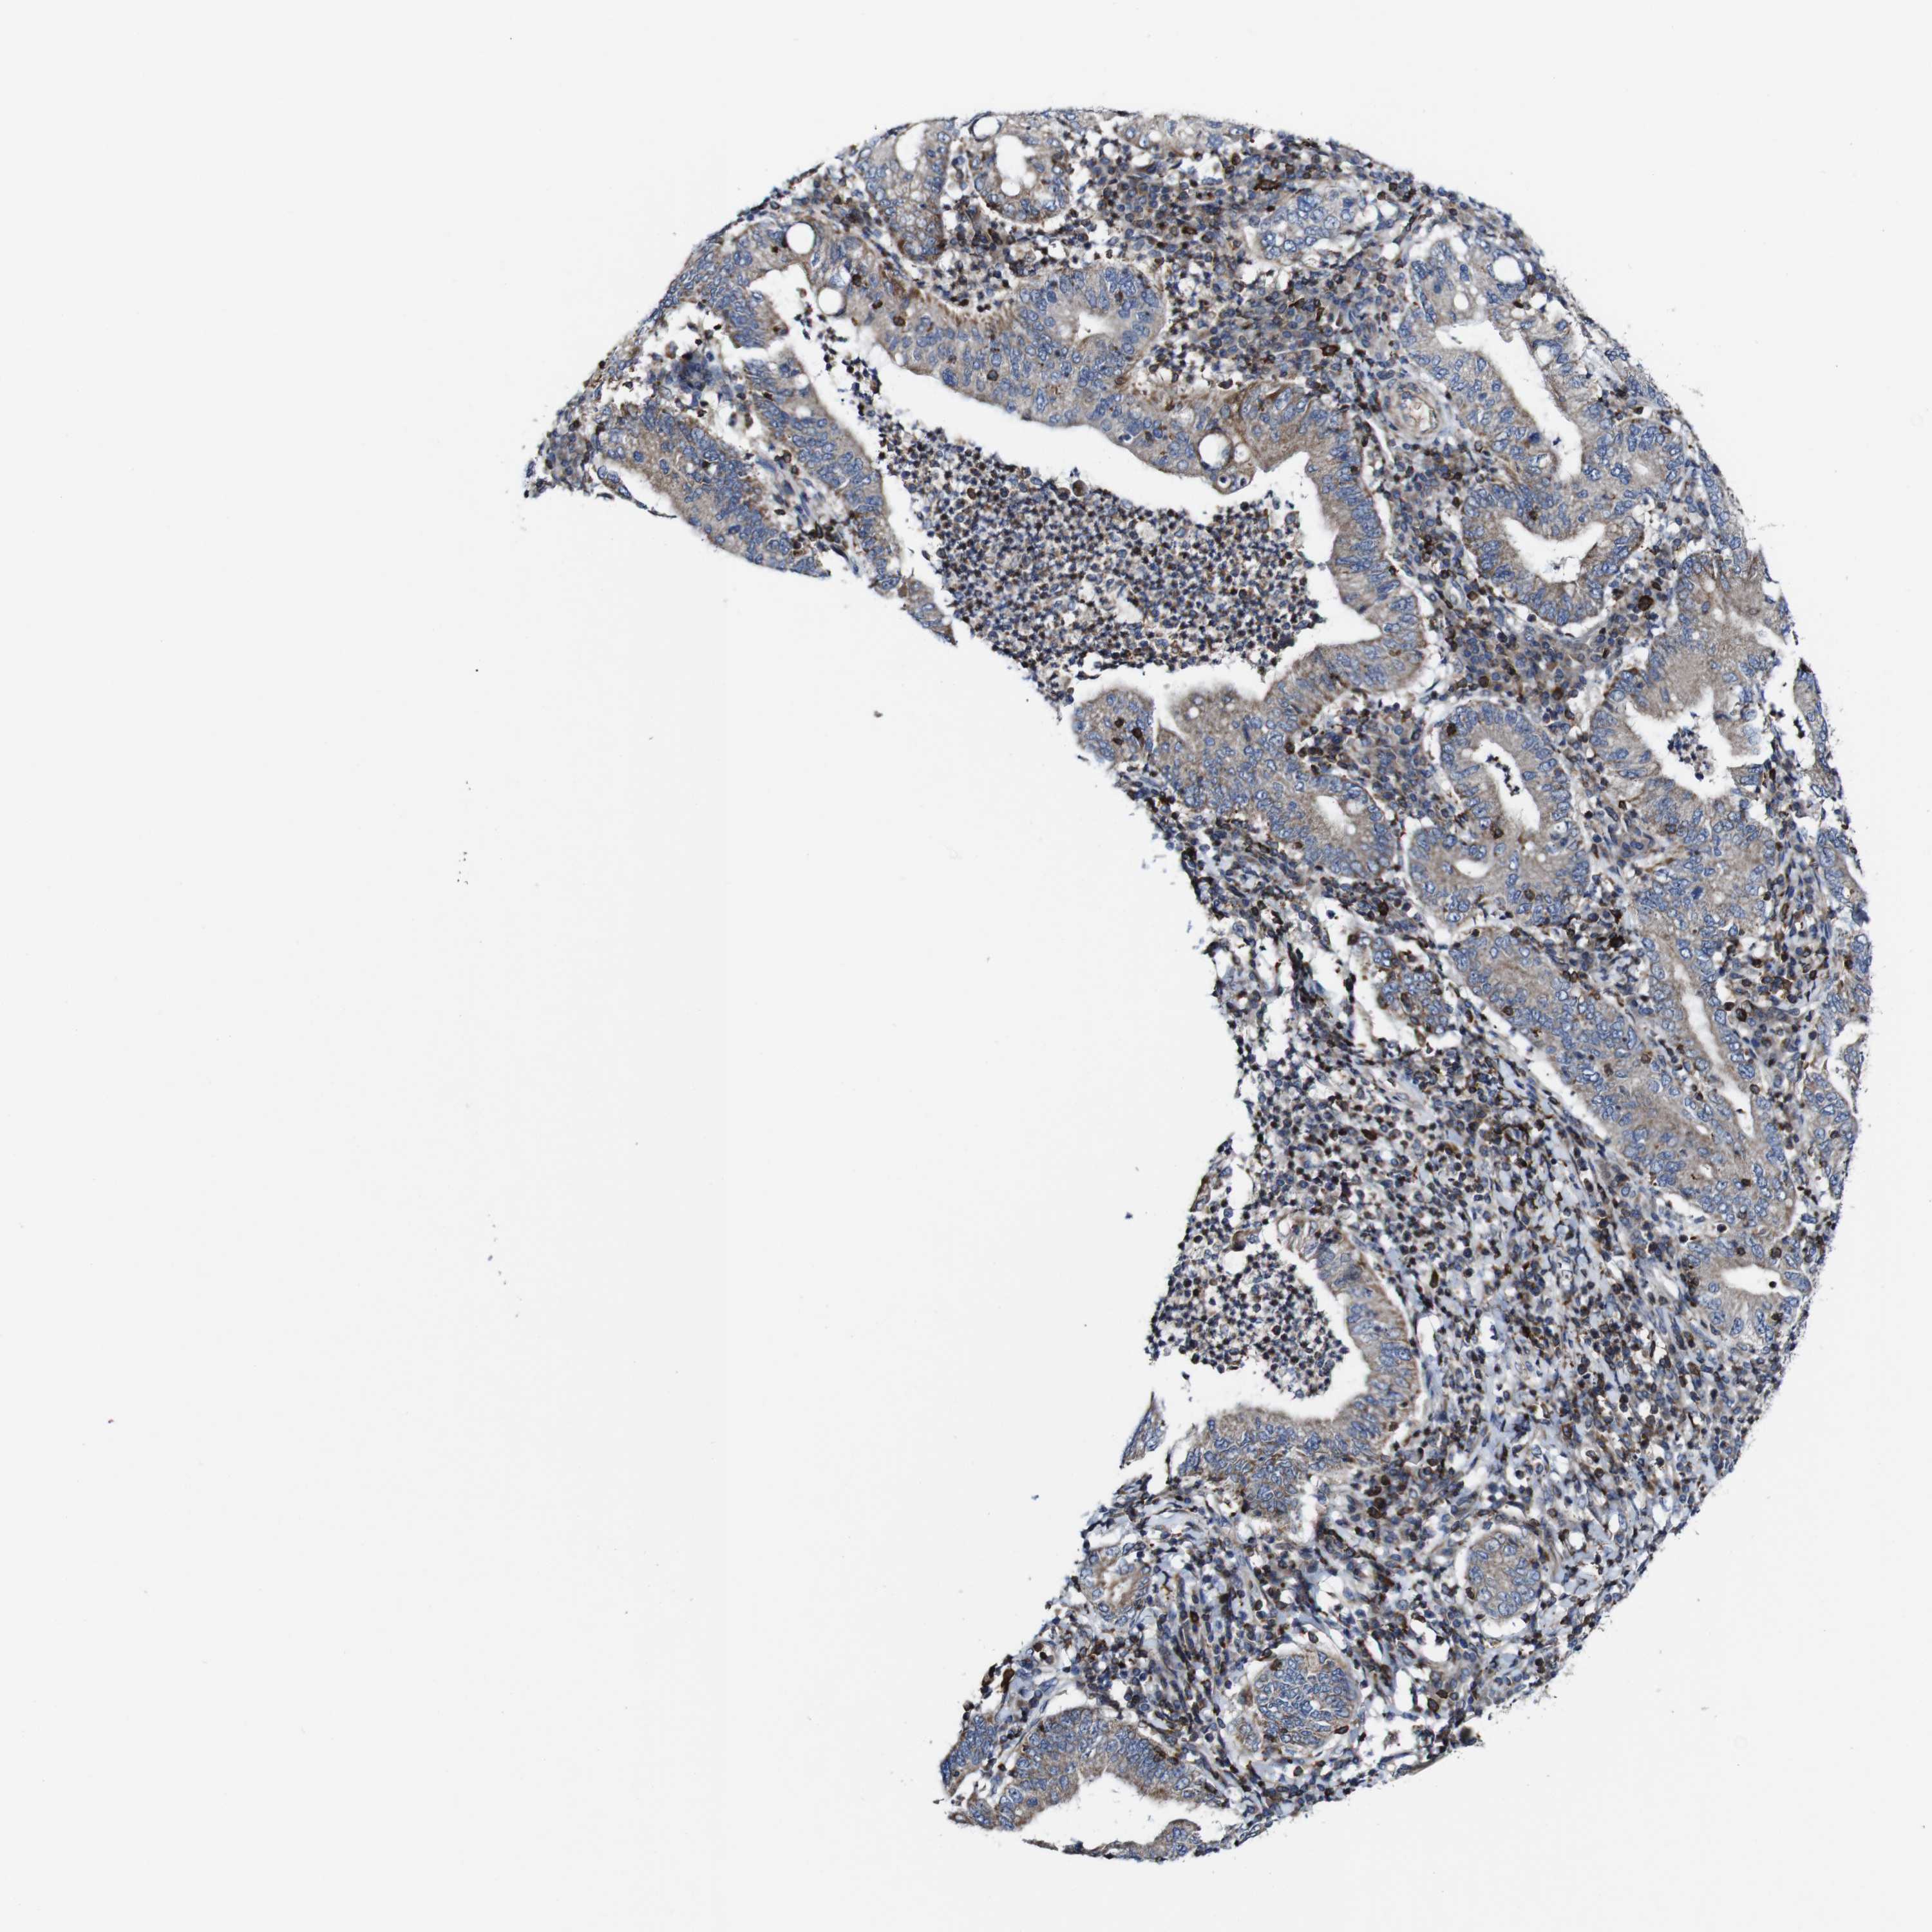

STOMACH CANCER - Protein expressioni

A mouse-over function shows sample information and annotation data. Click on an image to view it in a full screen mode. Samples can be filtered based on level of antibody staining by selecting one or several of the following categories: high, medium, low and not detected. The assay and annotation is described here.

Note that samples used for immunohistochemistry by the Human Protein Atlas do not correspond to samples in the TCGA dataset.

Antibody stainingi

Antibody staining in the annotated cell types in the current human tissue is reported as not detected, low, medium, or high, based on conventional immunohistochemistry profiling in selected tissues. This score is based on the combination of the staining intensity and fraction of stained cells.

Each image is clickable and will lead to virtual microscopy that enables deeper exploration of all samples and also displays staining intensity scores, fraction scores and subcellular localization as well as patient and tissue information for each sample.

Antibody HPA040820

Antibody CAB013089

Staining

High

Medium

Low

Not detected

Intensity

Strong

Moderate

Weak

Negative

Quantity

>75%

75%-25%

<25%

None

Location

Nuclear

Cytoplasmic/membranous

Cytoplasmic/membranous,nuclear

Adenocarcinoma, NOS